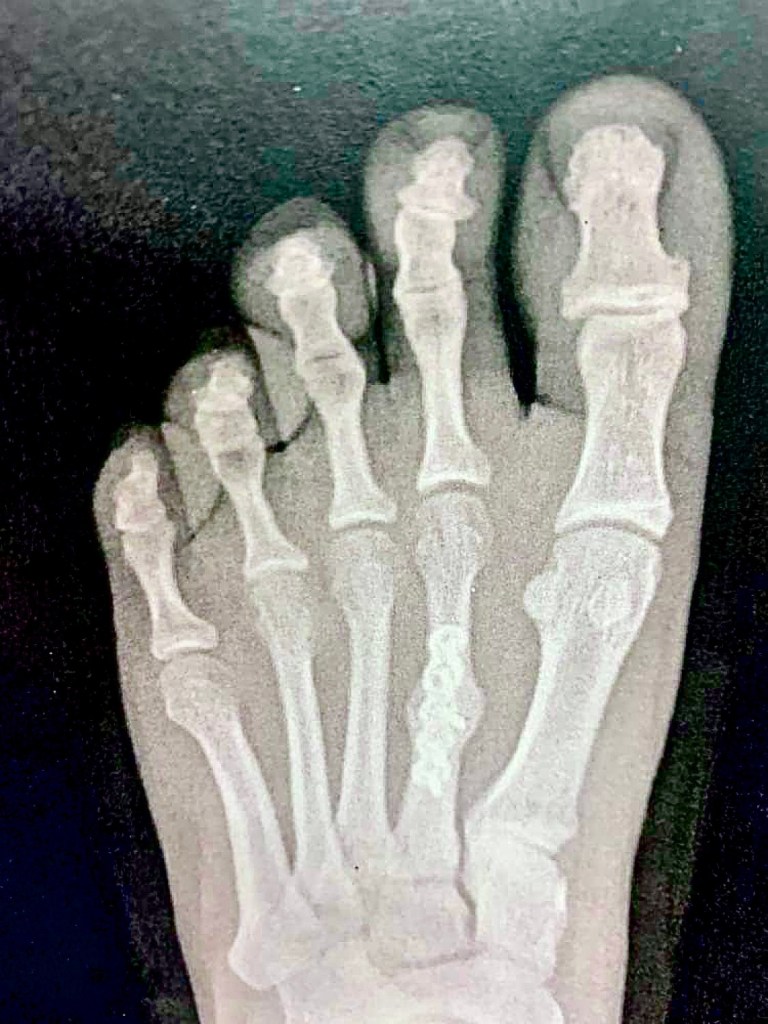

I broke one small bone in the middle of my foot. I did get it fixed and metal screws were put in to stabilize it. I can still walk on it and I only have a long scar. So everything is fine, right?

I thought I understood what she meant. But then my whole leg would hurt because my foot got too cold. My right leg, the uninjured one, would always be tired because when my left foot is hurting, I lean on my right leg. When I got sick, I dreaded getting up and getting me food or even going to the bathroom because that meant I had to walk. And walking HURT when I was sick.

A break to one little bone causes so much discomfort and pain. Because it’s not just one individual bone. But it’s a bone that’s a part of a system, a part of a body. It’s not only just the one bone that needs to heal, but my body too.